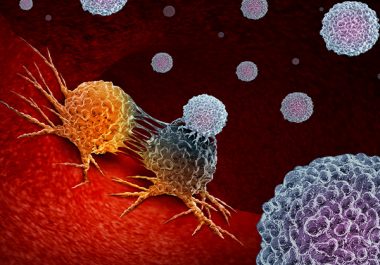

Lorazepam used to relieve stress may cause inflammation that promotes tumor growth and shortens progression-free survival, study says. A medication commonly used to ease the stress caused by cancer diagnosis and treatment may be...